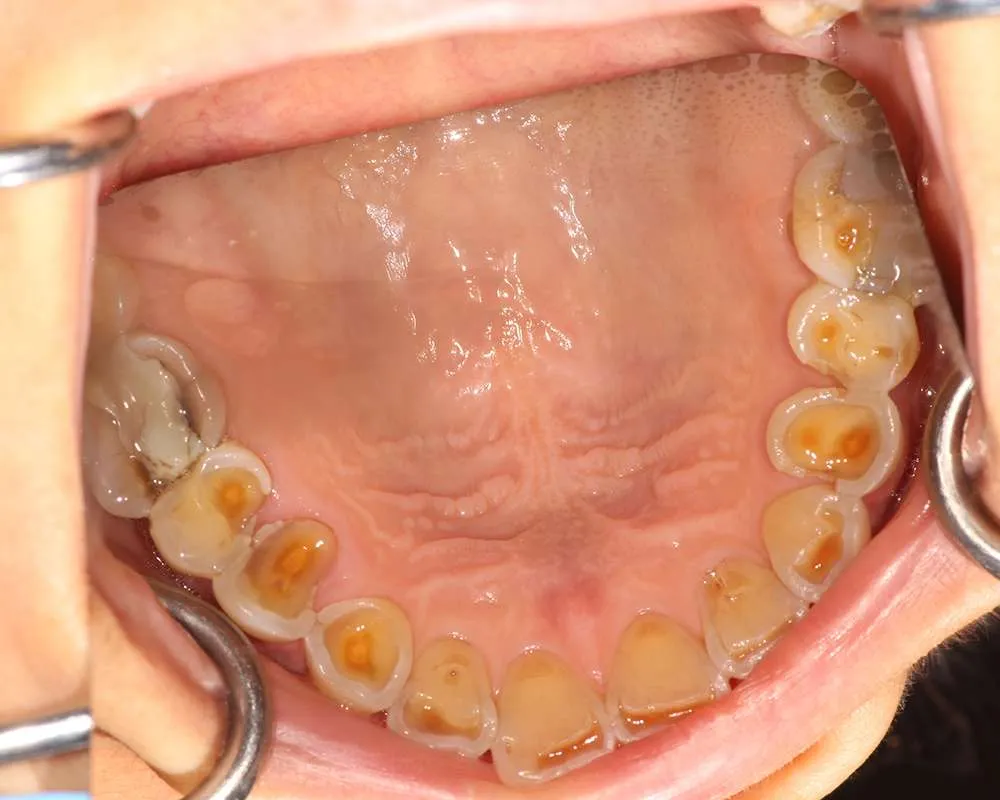

Real Stories, Real Results: Case Studies Showcasing How Our Personalized Approach Transforms Smiles and Lives

Witness the Remarkable Changes We Can Achieve

The safe removal of mercury fillings is crucial for your health and well-being. At our practice, we follow strict protocols to ensure that mercury amalgam fillings are removed safely and effectively.